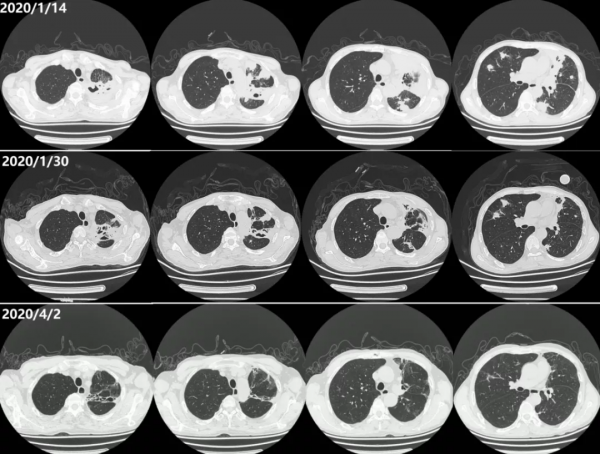

3、胸部CT(2020/1/4):右肺上葉及左肺多發高密度灶,較2019/12/19病灶增大(圖3)。

經治療,患者體溫正常,呼吸道症狀減輕,複查感染指標恢復正常(圖10),12月30日複查胸部CT提示肺部病灶較2020/1/14範圍縮小(圖11)。2月6日好轉出院。

出院後繼續口服「複方磺胺甲噁唑 1200mg/次 Q6H,潑尼松 25mg/日,硫酸羥氯喹 200mg 2次/日,白芍總苷 0.6g 3次/日」等。4月2日複查胸部CT兩肺病灶已明顯吸收(圖10)。

圖11:2020/4/2、2020/1/30及2020/1/14胸部CT對比